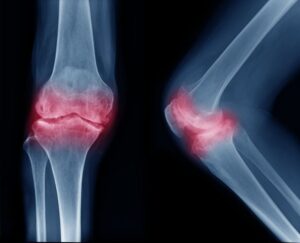

Kemik dokusunda anormal hücre büyümesidir. İyi huylu veya kötü huylu olabilir. İyi huylu tümörler yayılmazken, kötü huylular kanserleşebilir. Kemik tümörü kemikte ağrı, şişlik ve hareket kısıtlılığı yapar. Kesin tanı, röntgen, MR ve biyopsi ile konur. Tedavi; cerrahi, kemoterapi veya radyoterapi ile yapılır. Erken teşhis önemlidir.

Ağrı, en yaygın belirtisidir. Özellikle gece veya dinlenme sırasında artan bir ağrı görülebilir. Ağrı sürekli ve ilerleyici hale gelebilir. Bulunduğu bölgede şişlik veya belirgin bir kitle oluşabilir. Şişlik sert ya da yumuşak olabilir ve zamanla büyüyebilir. Kemik tümörü olan bölgede dokunmaya karşı hassasiyet oluşabilir. Hareket sırasında eklemlerde sertlik ve kısıtlılık görülebilir. Kemiğin zayıflamasına neden olabilir. Hafif darbelerde veya kendiliğinden oluşan patolojik kırıklar meydana gelebilir.

Ağrı, en yaygın belirtisidir. Özellikle gece veya dinlenme sırasında artan bir ağrı görülebilir. Ağrı sürekli ve ilerleyici hale gelebilir. Bulunduğu bölgede şişlik veya belirgin bir kitle oluşabilir. Şişlik sert ya da yumuşak olabilir ve zamanla büyüyebilir. Kemik tümörü olan bölgede dokunmaya karşı hassasiyet oluşabilir. Hareket sırasında eklemlerde sertlik ve kısıtlılık görülebilir. Kemiğin zayıflamasına neden olabilir. Hafif darbelerde veya kendiliğinden oluşan patolojik kırıklar meydana gelebilir.

Özellikle kötü huylu tümörlerde kilo kaybı ve genel halsizlik görülebilir. Tümörün ilerlemesine bağlı olarak iştahsızlık gelişebilir. Bazı kötü huylu tümörlerde açıklanamayan ateş ve gece terlemeleri olabilir. Bu durum bağışıklık sisteminin tümöre karşı verdiği yanıtla ilişkilidir. Tümörün bulunduğu bölgede ciltte kızarıklık ve ısı artışı oluşabilir. Tümör sinirlere baskı yaparsa, uyuşma, karıncalanma veya güç kaybı gibi belirtiler ortaya çıkabilir. Bu belirtiler başka hastalıklarla da ilişkili olabilir. Kemik tümörü teşhisi için mutlaka ortopedi uzmanına veya onkoloji doktoruna danışmak gereklidir. Röntgen, MRI ve biyopsi gibi tanı yöntemleri kesin teşhis koymaya yardımcı olur.